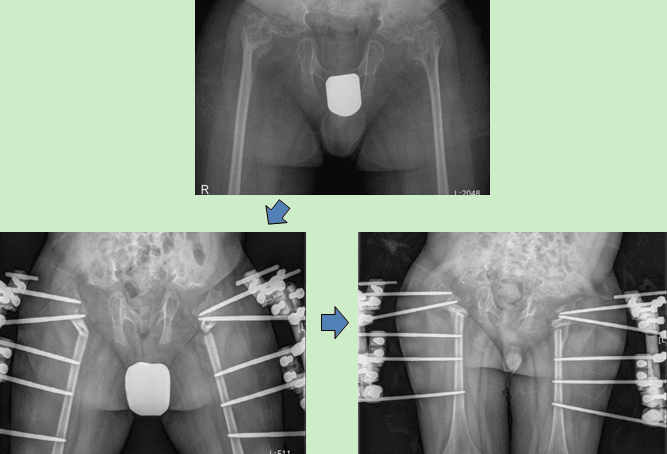

척추골단이형성증 환자로 보행이 불편하고 척추기 휘어 고관절 교정술을 시행하였습니다.

Hip joint correction was performed on the patient with spondyloepiphyseal dysplasia due to difficulties in walking and deformed spine.